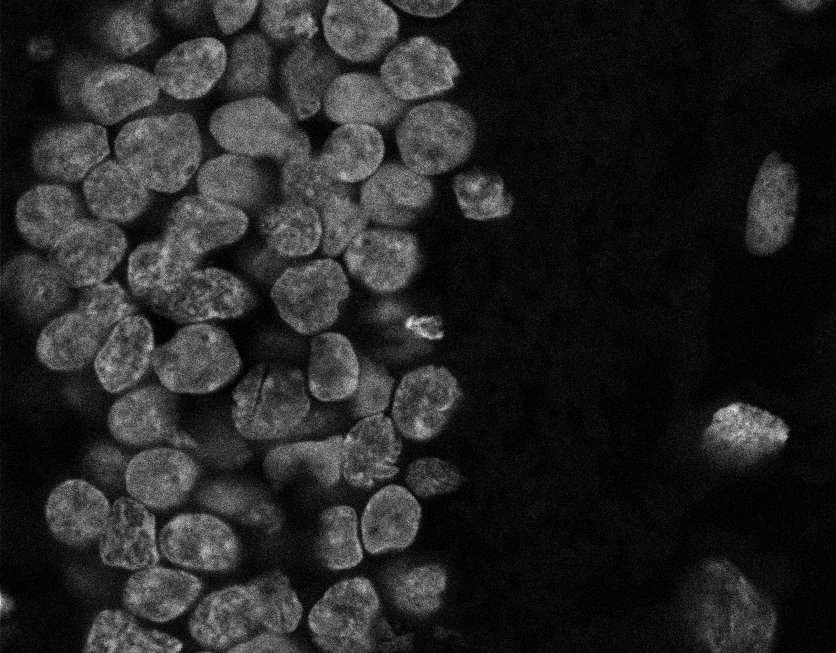

Nuclei

Nuclei - Bis

Nuclei - Bip

Nuclei - Bipolar